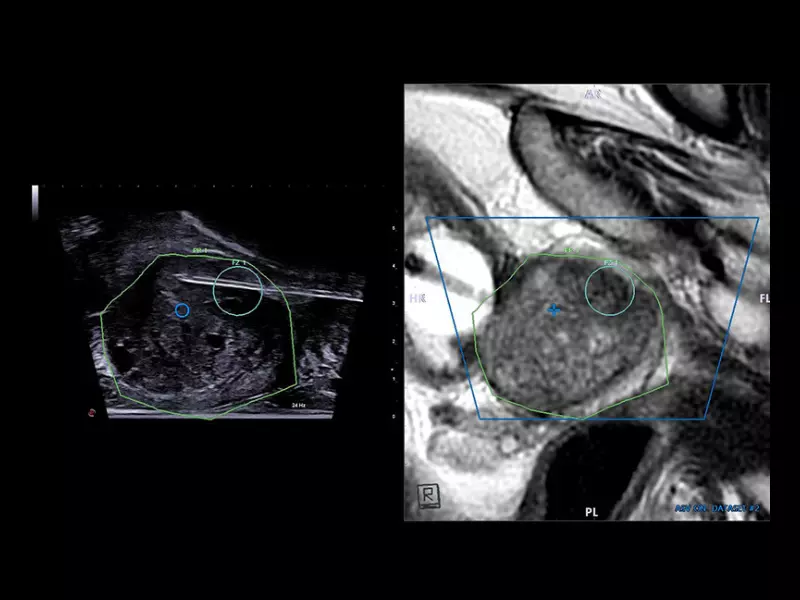

MyLab™X90 - UroFusion Automatic segmentation of the prostate MRI/US, followed by autoregistration of both modalities for targeted biopsies

MyLab™X90 - UroFusion Automatic segmentation of the prostate MRI/US, followed by autoregistration of both modalities for targeted biopsies